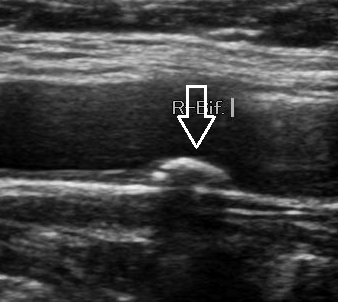

- 초음파 검사 시행

- 침대에 누워 목 양쪽에 초음파 탐촉자(probe)를 대고 관찰

- 의사가 협착 정도 및 IMT 수치, 혈류 이상 등을 설명